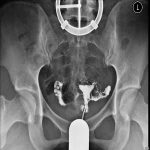

我曾经写过一篇名为《带瘤怀孕凶多吉少》的文章,强调了必须先除去子宫肌瘤,确保房间干净,然后再迎接宝宝的到来。通过B超检查可以做出诊断。全景四维彩超、阴道B超和腹部B超都能较为准确地确定对身体产生影响的肌瘤,不仅可以发现子宫肌瘤的数量,还可以确定其位置。仅仅依靠B超、症状和体征进行诊断,就不会出现误诊的情况。